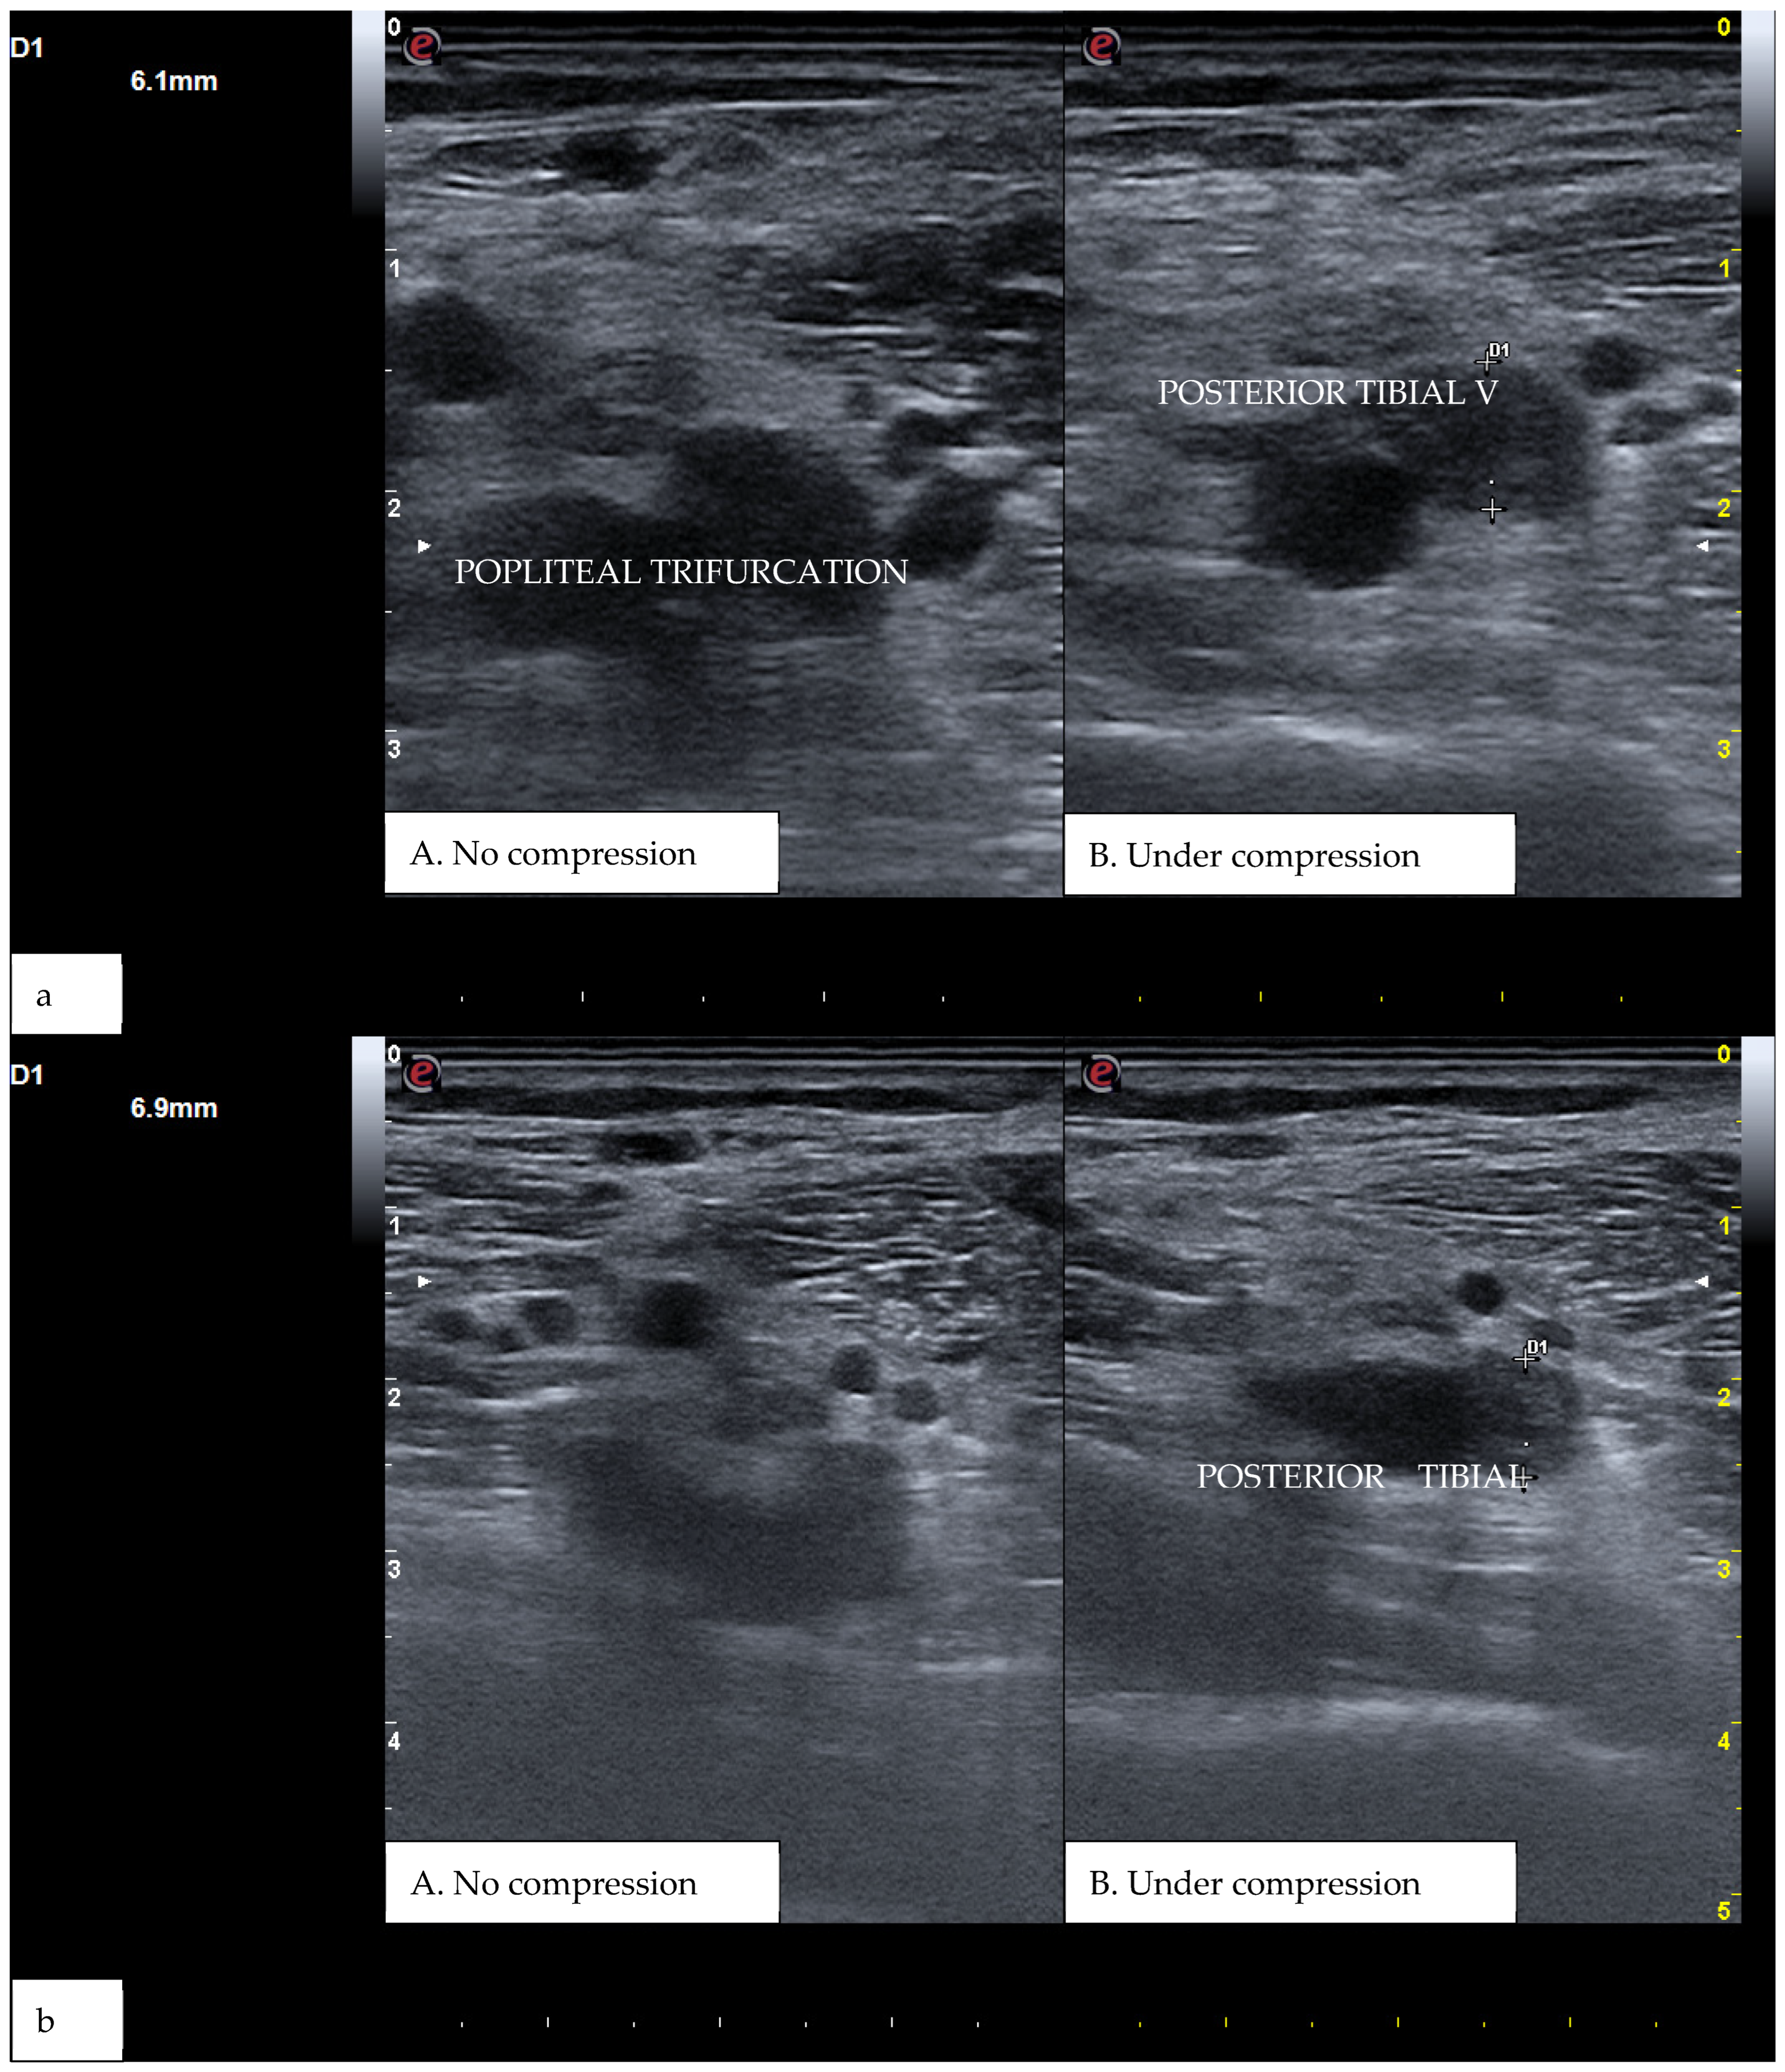

CUS is a diagnostic technique primarily designed to find DVT by checking the veins’ compressibility with the principle that healthy veins are normally compressible and would collapse under the pressure of the ultrasonographic probe. In the case of the presence of a venous thrombus, the vessel would not be able to collapse under such pressure [8,9]. Linear high-frequency transducers are generally used for CUS as they best visualize leg veins [10]. The ultrasound machine settings must be adjusted carefully in order to limit possible operator-related bias. Important elements to be considered in this setting include gain, focus, and time-gain compensation. Gain adjustment regulates image brightness, focus optimization sharpens the image to the desired depth, and time-gain compensation enhances the visibility of subtle echoes, ensuring uniform image quality [10,11]. The transducer partially compresses the vein, which creates an echogenic response. In normal veins, this technique should fully compress the lumen [9]. However, with thrombosis present, the vein does not collapse enough, which causes a non-continuous echogenic line [12]. While the femoral veins are usually well identified in the groin and thigh areas, to facilitate better visibility of the popliteal veins, the patient may lie in a supine position with the leg slightly abducted to relax the muscles or, alternatively, in a prone position [9]. Real-time B-mode and Doppler imaging are both valuable tools in this process. B-mode imaging can find incomplete vein collapse during compression [13,14]. Doppler imaging can show the thrombus or find a complete lack of flow in the lumen [9]. As such, CUS for DVT diagnosis involves evaluating direct signs like the presence of a non-compressible echogenic line suggesting a thrombus, as well as indirect signs like changes in vein compressibility and thrombus echogenicity [6,7]. In addition, evaluation of flow patterns and flow response during augmentation maneuvers may refine the diagnostic examination, although their implementation requires more advanced training and skills than simple CUS [7]. Clinicians should assess a spectrum of veins, including the external iliac, common femoral, superficial and deep femoral, popliteal, tibial, peroneal, gastrocnemial, and soleal veins, as well as the junctions with the great and small saphenous veins, representing the superficial systems [15]. Challenges exist in visualizing the iliac veins, especially in obese patients, yet phasic flow in the femoral veins can be indicative of DVT status, particularly for excluding iliac vein thromboses [16]. This comprehensive approach is standard in differentiating healthy veins, which should collapse and enlarge with augmentation maneuvers, from those with thrombosis, which show impaired response to pressure and flow changes [12,17]. Figure 1, Figure 2, Figure 3 and Figure 4 show real examples of DVT affecting different sites of the lower limb deep venous system, diagnosed through a CUS modality.

Figure 3. (a) A real example of DVT at the level of the right popliteal trifurcation with posterior tibial vein involvement. (b) Represents the same patient at a more distal section. D1 shows the residual diameter of the non-compressible vein (i.e., the maximum diameter of the relative venous thrombus).